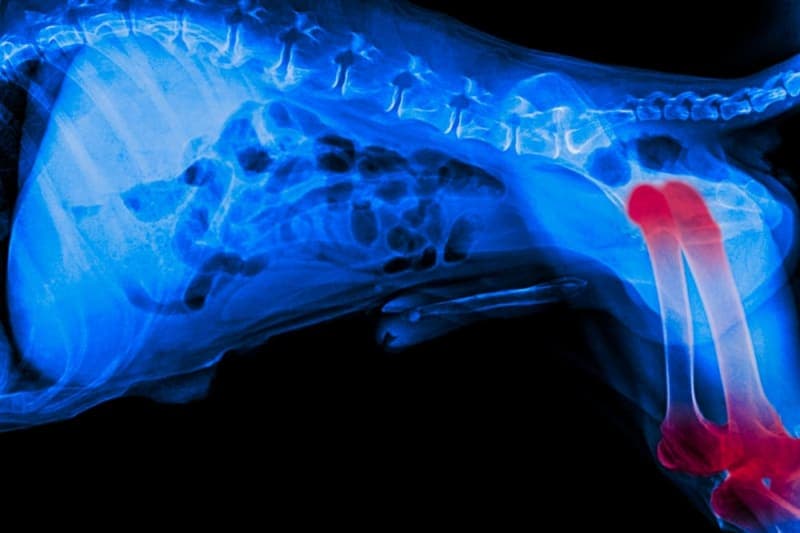

Osteoarthritis in Dogs

Osteoarthritis is a progressive, degenerative condition in dogs that becomes more severe over time. Although there is no cure for this painful condition, symptoms can often be successfully managed to help your dog enjoy a good quality of life as they continue to age with osteoarthritis.

Osteoarthritis is the most common form of arthritis in dogs and is a degenerative joint disorder that leads to a permanent deterioration of the cartilage that provides cushioning for the joints. This painful condition is estimated to affect about a quarter of all dogs throughout their lifetime. Osteoarthritis can be in a dog's back legs, front legs, or all four.

- Swollen joints